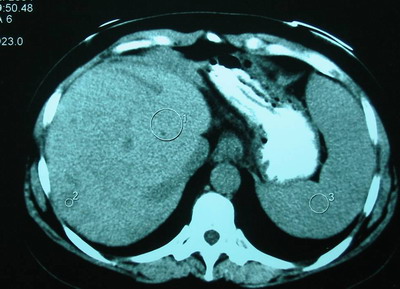

肝脏CT:考虑肝血管瘤,肝右叶血管弧形移位。

肝MRI:肝右叶异常信号――符合血管瘤肝形态,血管改变——考虑发育异常。